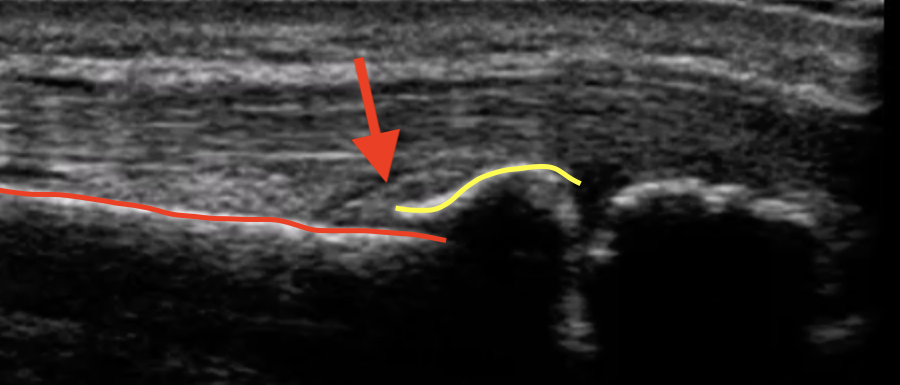

骨が変形して、骨のライン(赤線と黄色線)がずれてしまっています

整復操作をして骨のラインが元通りになっています